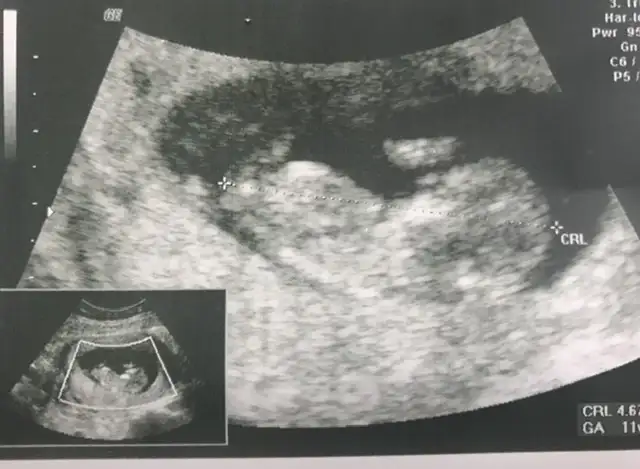

Merhabalar Ikra meyra Ikra meyra sizden rica etsem benim icinde tahminde bulunmaniz mumkunmu bugun gittim normalde sat a gore 8+4 ama doktorum 9+3 gorunuyor cok iyi dedi tahminde bulunabilirmisiniz😊

Eklentiler

• 20200219_124552.webp

20200219_124552.webp

85,9 KB · Görüntüleme: 64